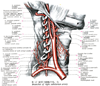

A12_2_08_043

下甲状腺動脈Inferior thyroid artery(Arteria thyroidea inferior)

下甲状腺動脈【かこうじょうせんどうみゃく】 Artery passing along the anterior border of the anterior scalene muscle to the level of the sixth cervical vertebra and then behind the common carotid artery to the thyroid gland.(下甲状腺動脈は沿う頚動脈の後方を内側へ走り、甲状腺下部にいたる。甲状腺に分布する腺枝のほかに、周囲気管への分枝として下喉頭動脈、咽頭枝、食道枝、気管枝を分岐する。)